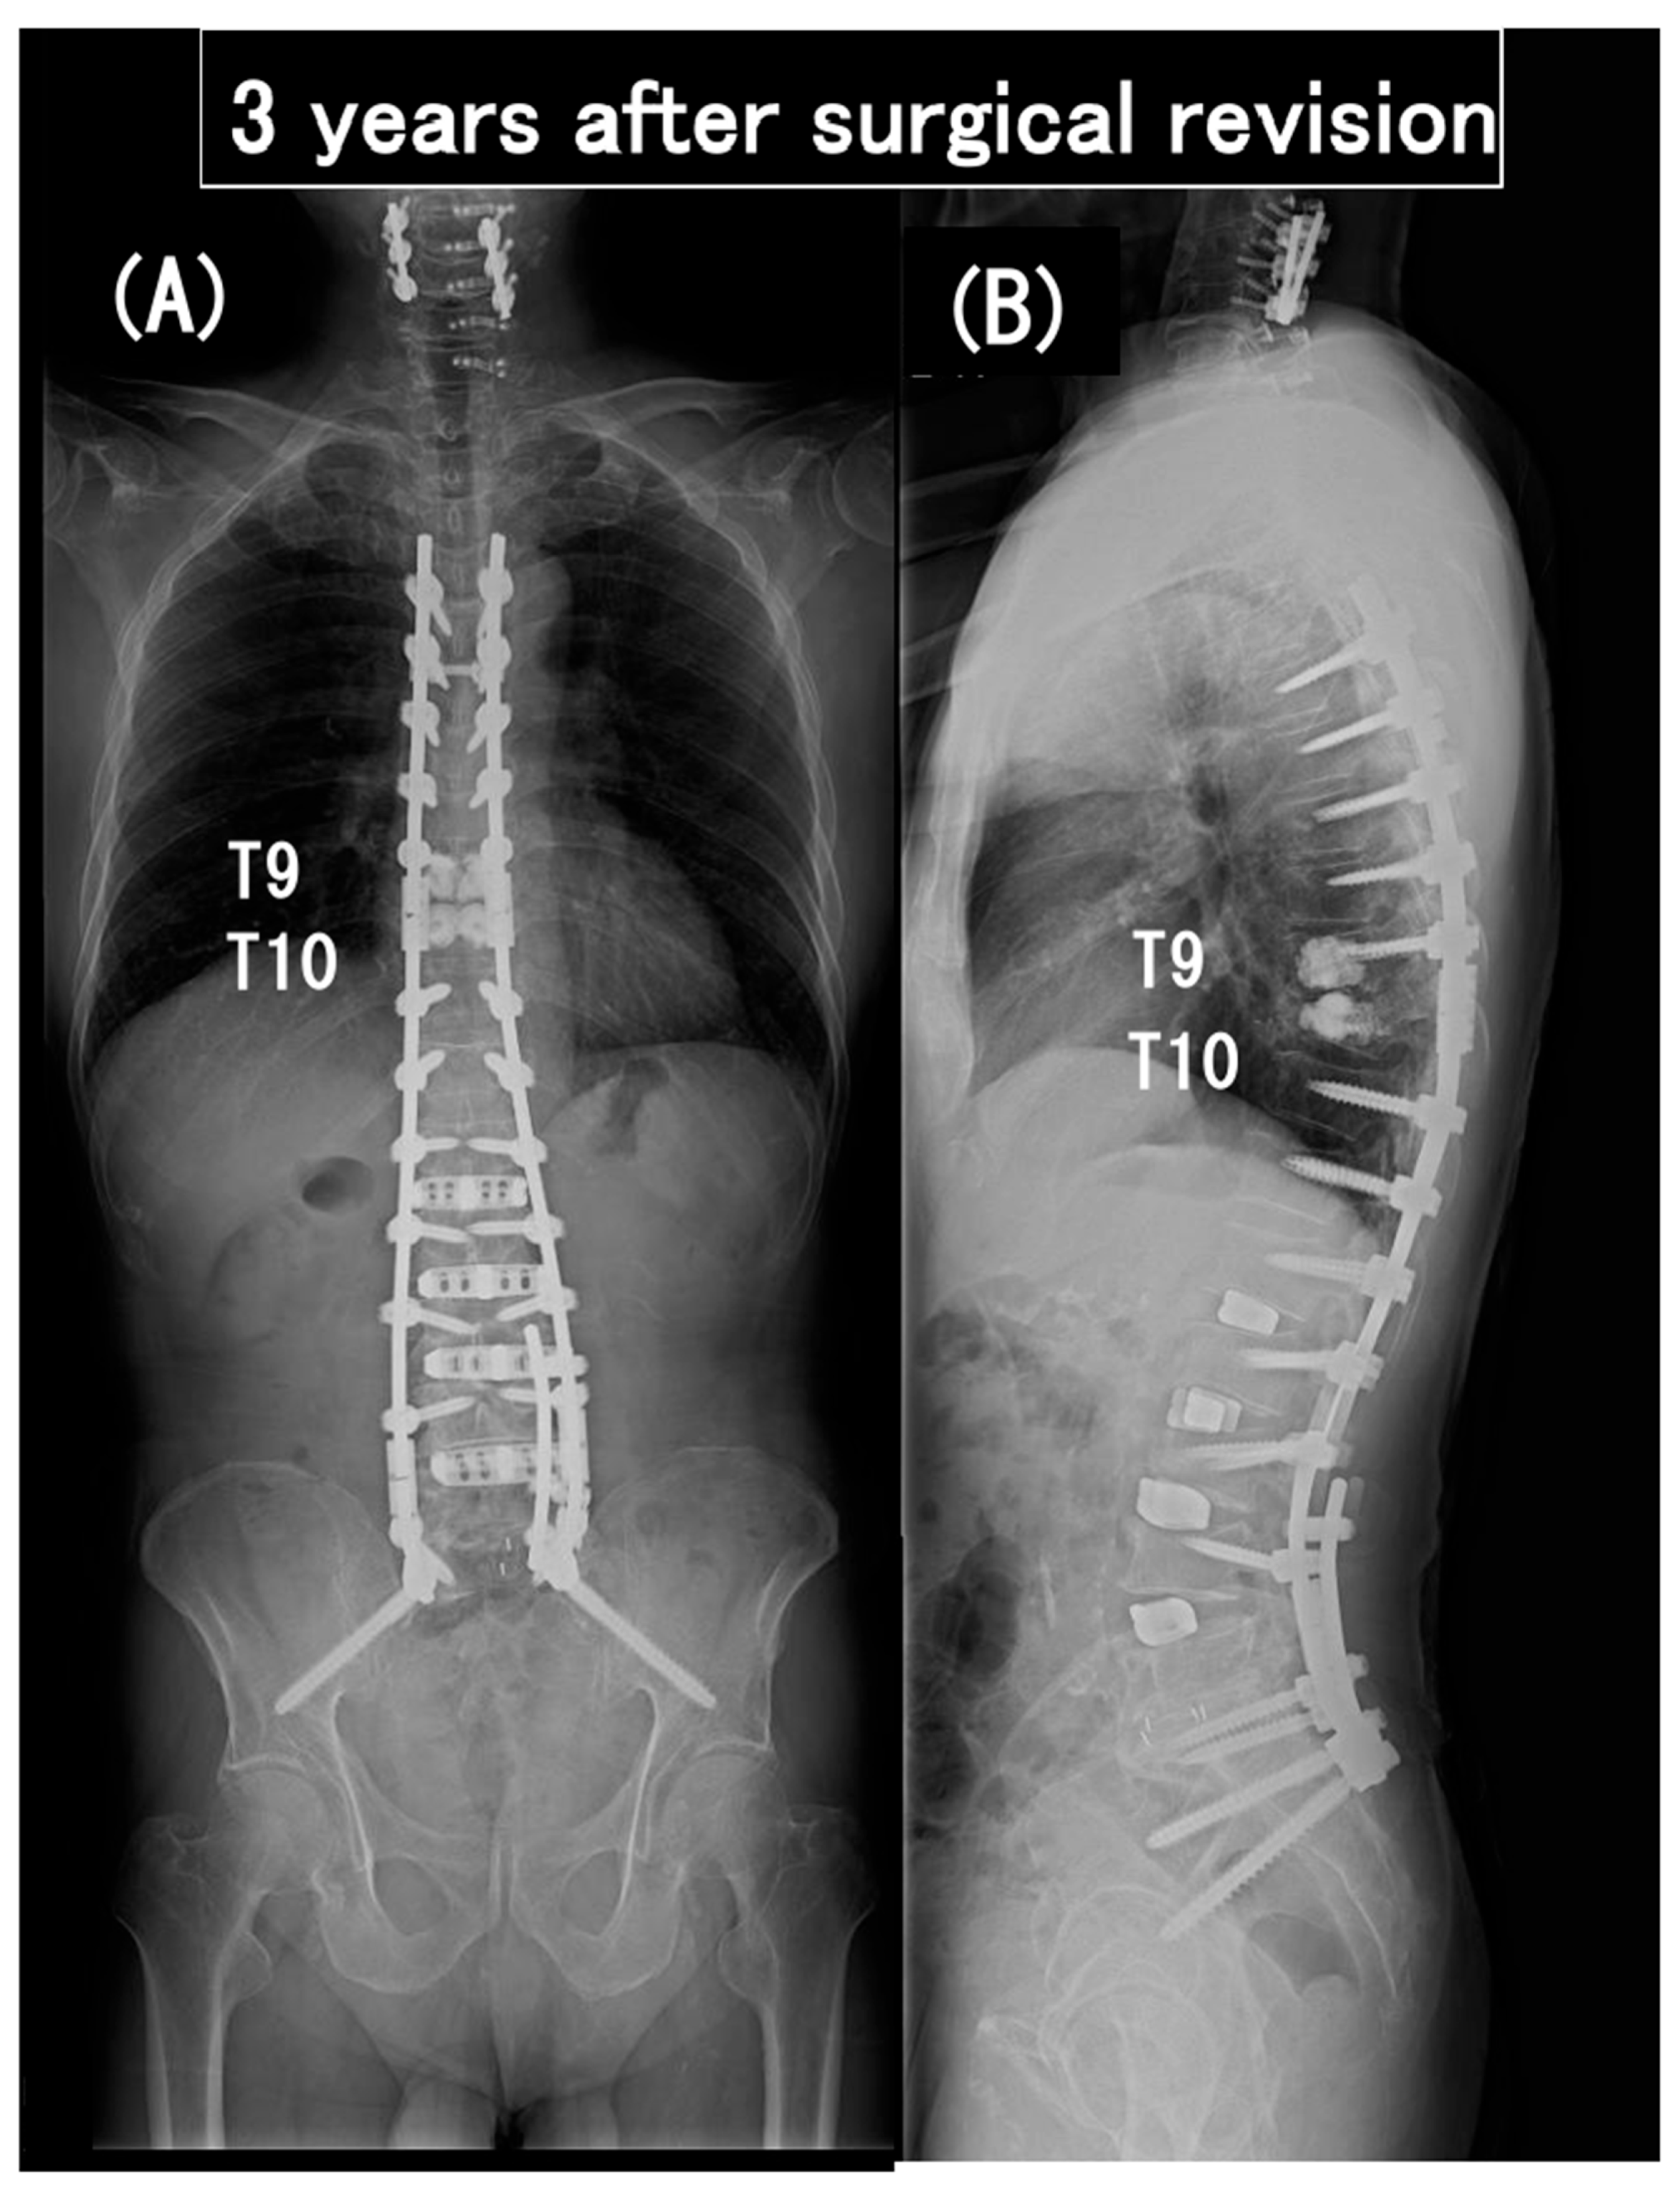

3.6. Case Presentation

- Case no. 6

- 2.

- Case no. 4